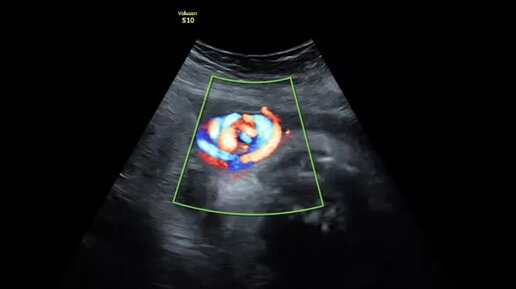

Истинный узел пуповины.